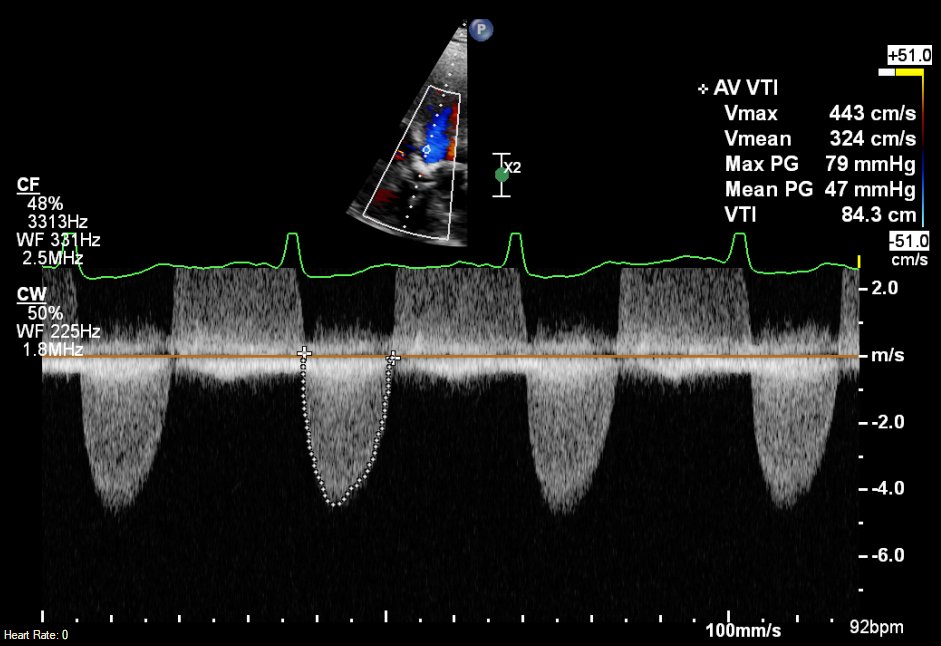

Thanks Benoy. You have illustrated why a request for an echo is always a request for an echo opinion not just a test. (in this case don’t do the test and treat the patient (really fast)). Medical culture pushes people (inc me) to organise tests without understanding the disease

@dr_benoy_n_shah

Question for the #echofirst community A patient with severe global LV dysfunction (EF ~20%) has high gradient severe AS You're asked to do low-dose dobutamine study to check for LV contractile reserve Please vote in next 2 polls, would love to know how practice varies around 🌍